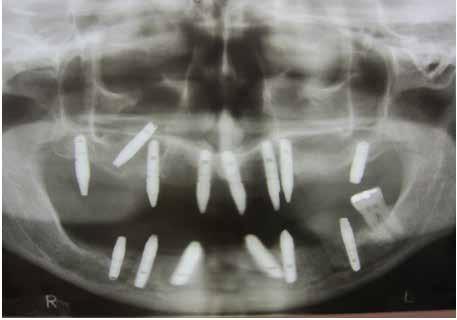

Ebben a cikkben egy 16 éves lánypáciens esetét szeretném bemutatni (1–7. képek)

A Pitts21-es fix készülékes kezelés során a harapásemelőket a felső nagyőrlő fogakra ragasztottuk, hogy a felső molárisok intrúziójával segítsék a harapás zárását (8. kép) Ún. keresztharapásos, majd később normál class 2-es gumihúzással (9–10. képek), továbbá az elülső fogakon alkalmazott ún. Rainbow harapás-záró gumihúzással (11. kép) korrigáltuk a jobb oldali teljes premolárisnyi distal-harapást, valamint az elülső nyitott harapást.

6 hónap után a nyitott harapás már nagyjából összezárásra került (12. kép)! A gumihordás a kezelés teljes hosszában folyamatos, éjjel-nappal, 22-24 órában az étkezések és az utánuk történő fogmosás kivételével.

A fix fogszabályozó készülék mindössze 16 hónapos kezelés után került eltávolításra! Páciensünk legnagyobb örömére állcsontműtét nélkül sikerült mind az arcesztétikai, mind a funkcionális rehabilitáció (13–18. képek)